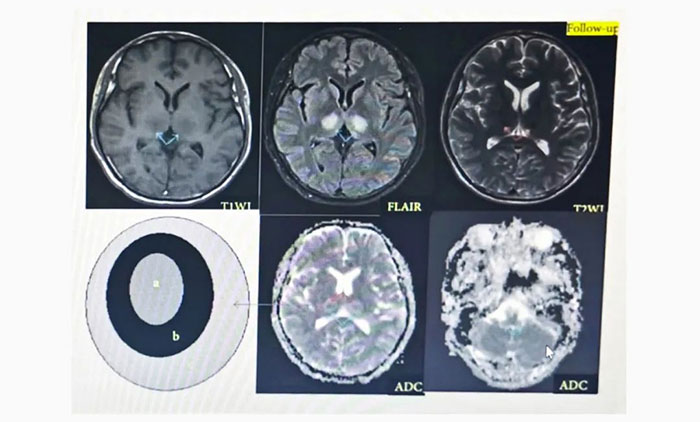

▲ ANE影像學(xué):具有多灶性、對(duì)稱性腦損害的特點(diǎn),病變內(nèi)出血和環(huán)形強(qiáng)化為經(jīng)典影像學(xué)表現(xiàn)。ADC加權(quán)像上呈特征性“同心圓結(jié)構(gòu)”。

▲ 患者影像變化